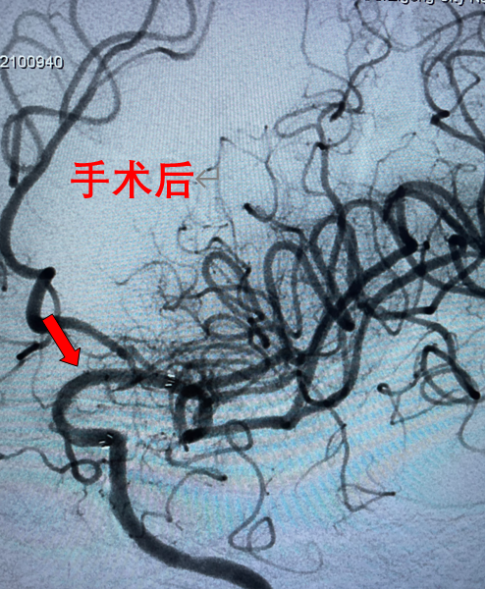

随着时间的推移,陈大爷病情不断加重,突然有一天他失去了意识,家人赶紧将他送到了自贡四院神经内科救治。经过专家的检查和诊断,陈大爷的病因找到了——左侧颈内动脉末段堵塞,导致了我们大家熟知的脑梗。

要解决陈大爷的问题,除了规范的药物治疗外,通过介入手术治疗的方式可能会达到更好的治疗效果。

做好术前准备后,陈大爷进入介入手术室,神经内科医务人员成功为其完成了“左侧颈内动脉末段血管成形、支架植入术”。

术后,陈大爷头晕、行走不稳等症状消失,恢复到正常状态。